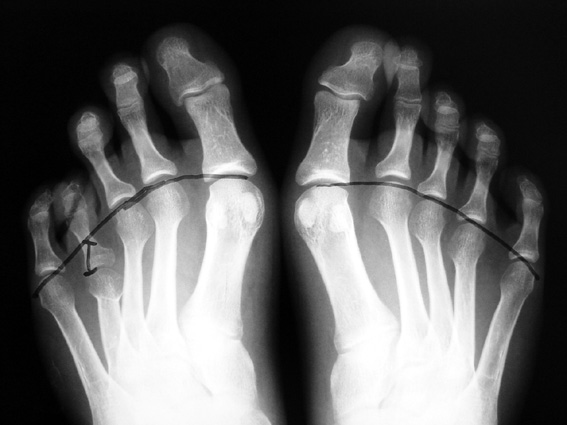

Finger (metacarpus) and toe (metatarsus) shortness can be seen congenitally as a single deformity or as a part of various syndromes; or after trauma or Freiberg disease (avascular necrosis). The frequency of congenital metacarpal or metatarsal shortness is less yhan 1/1000. It is seen 5 times more freqently in women and usually (72%) bilateral. Fourth finger is the most frequently involved. Although the cause of this problem is not known exactly, it is believed that the deformity is usually caused by early closure of the growth plate.

Surgical treatment may be required for metacarpal shortness because of cosmetic disturbance and fatigue in the dominant hand; and for metatarsal shortness because of cosmetic appearance, metatarsalgia, deformity due to dorsal shift of the short finger, pain and pressure ulcers due to plantar shift of the short finger, or difficulty in shoe wearing. Various techniques have been defined for the treatment of congenital metacarpal or metatarsal shortness. However, the most frequently used methods are acute lengthening with grafting, and distraction osteogenesis (callotasis). Callotasis method is preferred for lengthening more than 1 cm. In our department, we prefer distraction osteogenesis with unilateral or circular external fixator for lengthening of metacarpal and metatarsal bones.